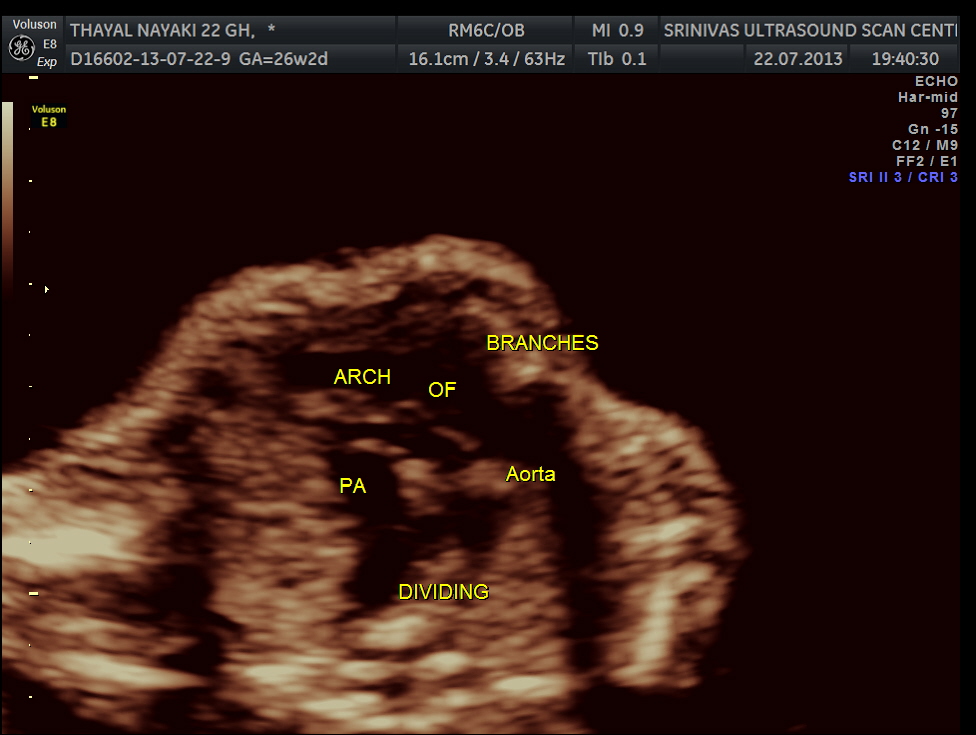

Under normal circumstances the chamber in front of descending aorta is left atrium ; and the aorta arises from the left ventricle which has no trabeculations ; the pumonary artery which divides into the two branches arises from the anterior right ventricle and crosses over the aorta .

next is the normal outflow tracts and the normal 3 vessel view and the normal arches.

here we can see the pulmonary artery with its two branches arising from the lower (left) ventricle .and the aorta arising from the anterior (right ) ventricle.

the following 3 D reconstructed image shows the parallel flow of the great arteries